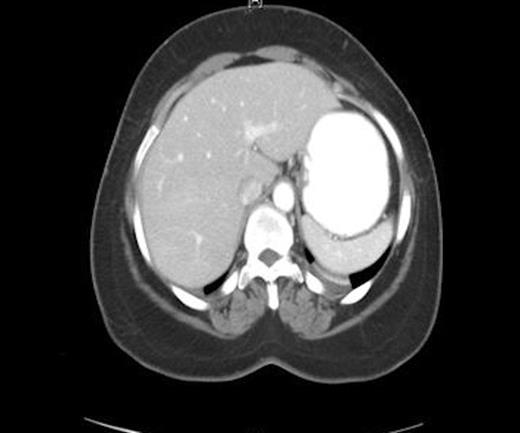

A 29 year - old African American male with Russel-Silver Dwarfism presented with one day history of diarrhea, nausea, vomiting, right side abdominal pain, and abdominal distention. The pain was constant, gradually increasing in severity, and not related to food intake. The patient denied fever and other gastrointestinal or genitourinary complains. His medical history was significant for Russel - Silver Dwarfism, calcium deficiency, cardiomegaly, and bilateral testicular implants for undescended testicles. The patient was sexually active only with his girlfriend and denied any history of sexually transmitted disease. On examination patient was afebrile and his vitals were stable. His abdomen was soft, mildly distended and diffusely tender on right side. There was no abdominal guarding, rigidity, or rebound tenderness. Laboratory workup revealed white blood cell (WBC) count of 14,000/L with normal liver function tests. Chest and abdominal radiographs appeared normal. CT scan of the abdomen and pelvis showed a small amount of free fluid in pelvis; the proximal appendix appeared normal, however the distal appendix was not visualized. The liver capsule appeared normal and there was no subcapsular fluid collection (figure 1).

CT scan showing normal appearing liver capsule and no perihepatic fluid collection